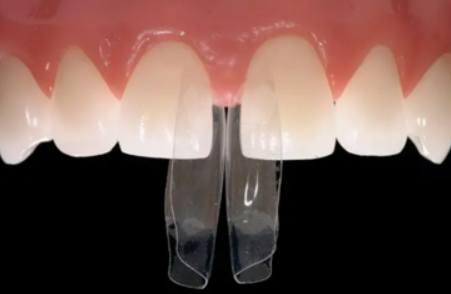

저는 Style Italiano의

UNICA PROXIMAL을 주로 사용해요.

제가 자주 쓰는 방법은 Style Italiano라는 레진 스터디 그룹에서 만든 ‘UNICA PROXIMAL’이에요.

이것은 바이오 클리어에서 나타나는 단점이 전혀 없이 앞니의 모양을 예쁘고 자연스럽게 잡을 수 있어요.

대신 한 가지 특징이 있어요.

앞니 사이를 꽉 막기보다는 아주 얇은, 자연스러운 공간이 남을 수 있다는 점인데요.